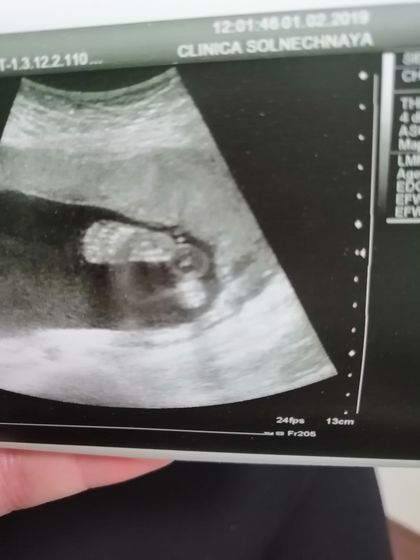

Девочки, приветик, сегодня был наш второй скрининг, все хорошо, малыша увидела, так соскучилась с прошлой встречи, такой забавный, уже совсем большой?

На первом фото пяточки?)))))

Да, пяточки?